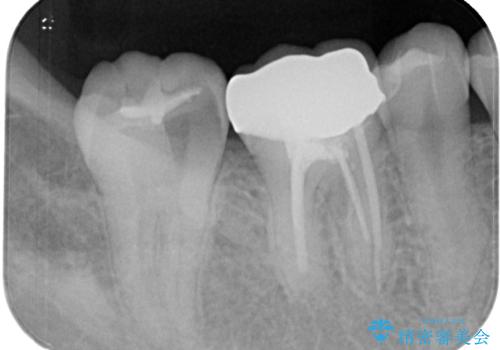

レントゲン撮影を行い、歯髄診査を行いました。歯髄の正常な反応を確認できたのでオールセラミッククラウンによる虫歯治療をすることにしました。

虫歯の上に歯茎が覆いかぶさっていたので、レーザーにて歯茎を除去し虫歯が大きいことが予想できたのでラバーダム防湿下で虫歯の除去をしました。